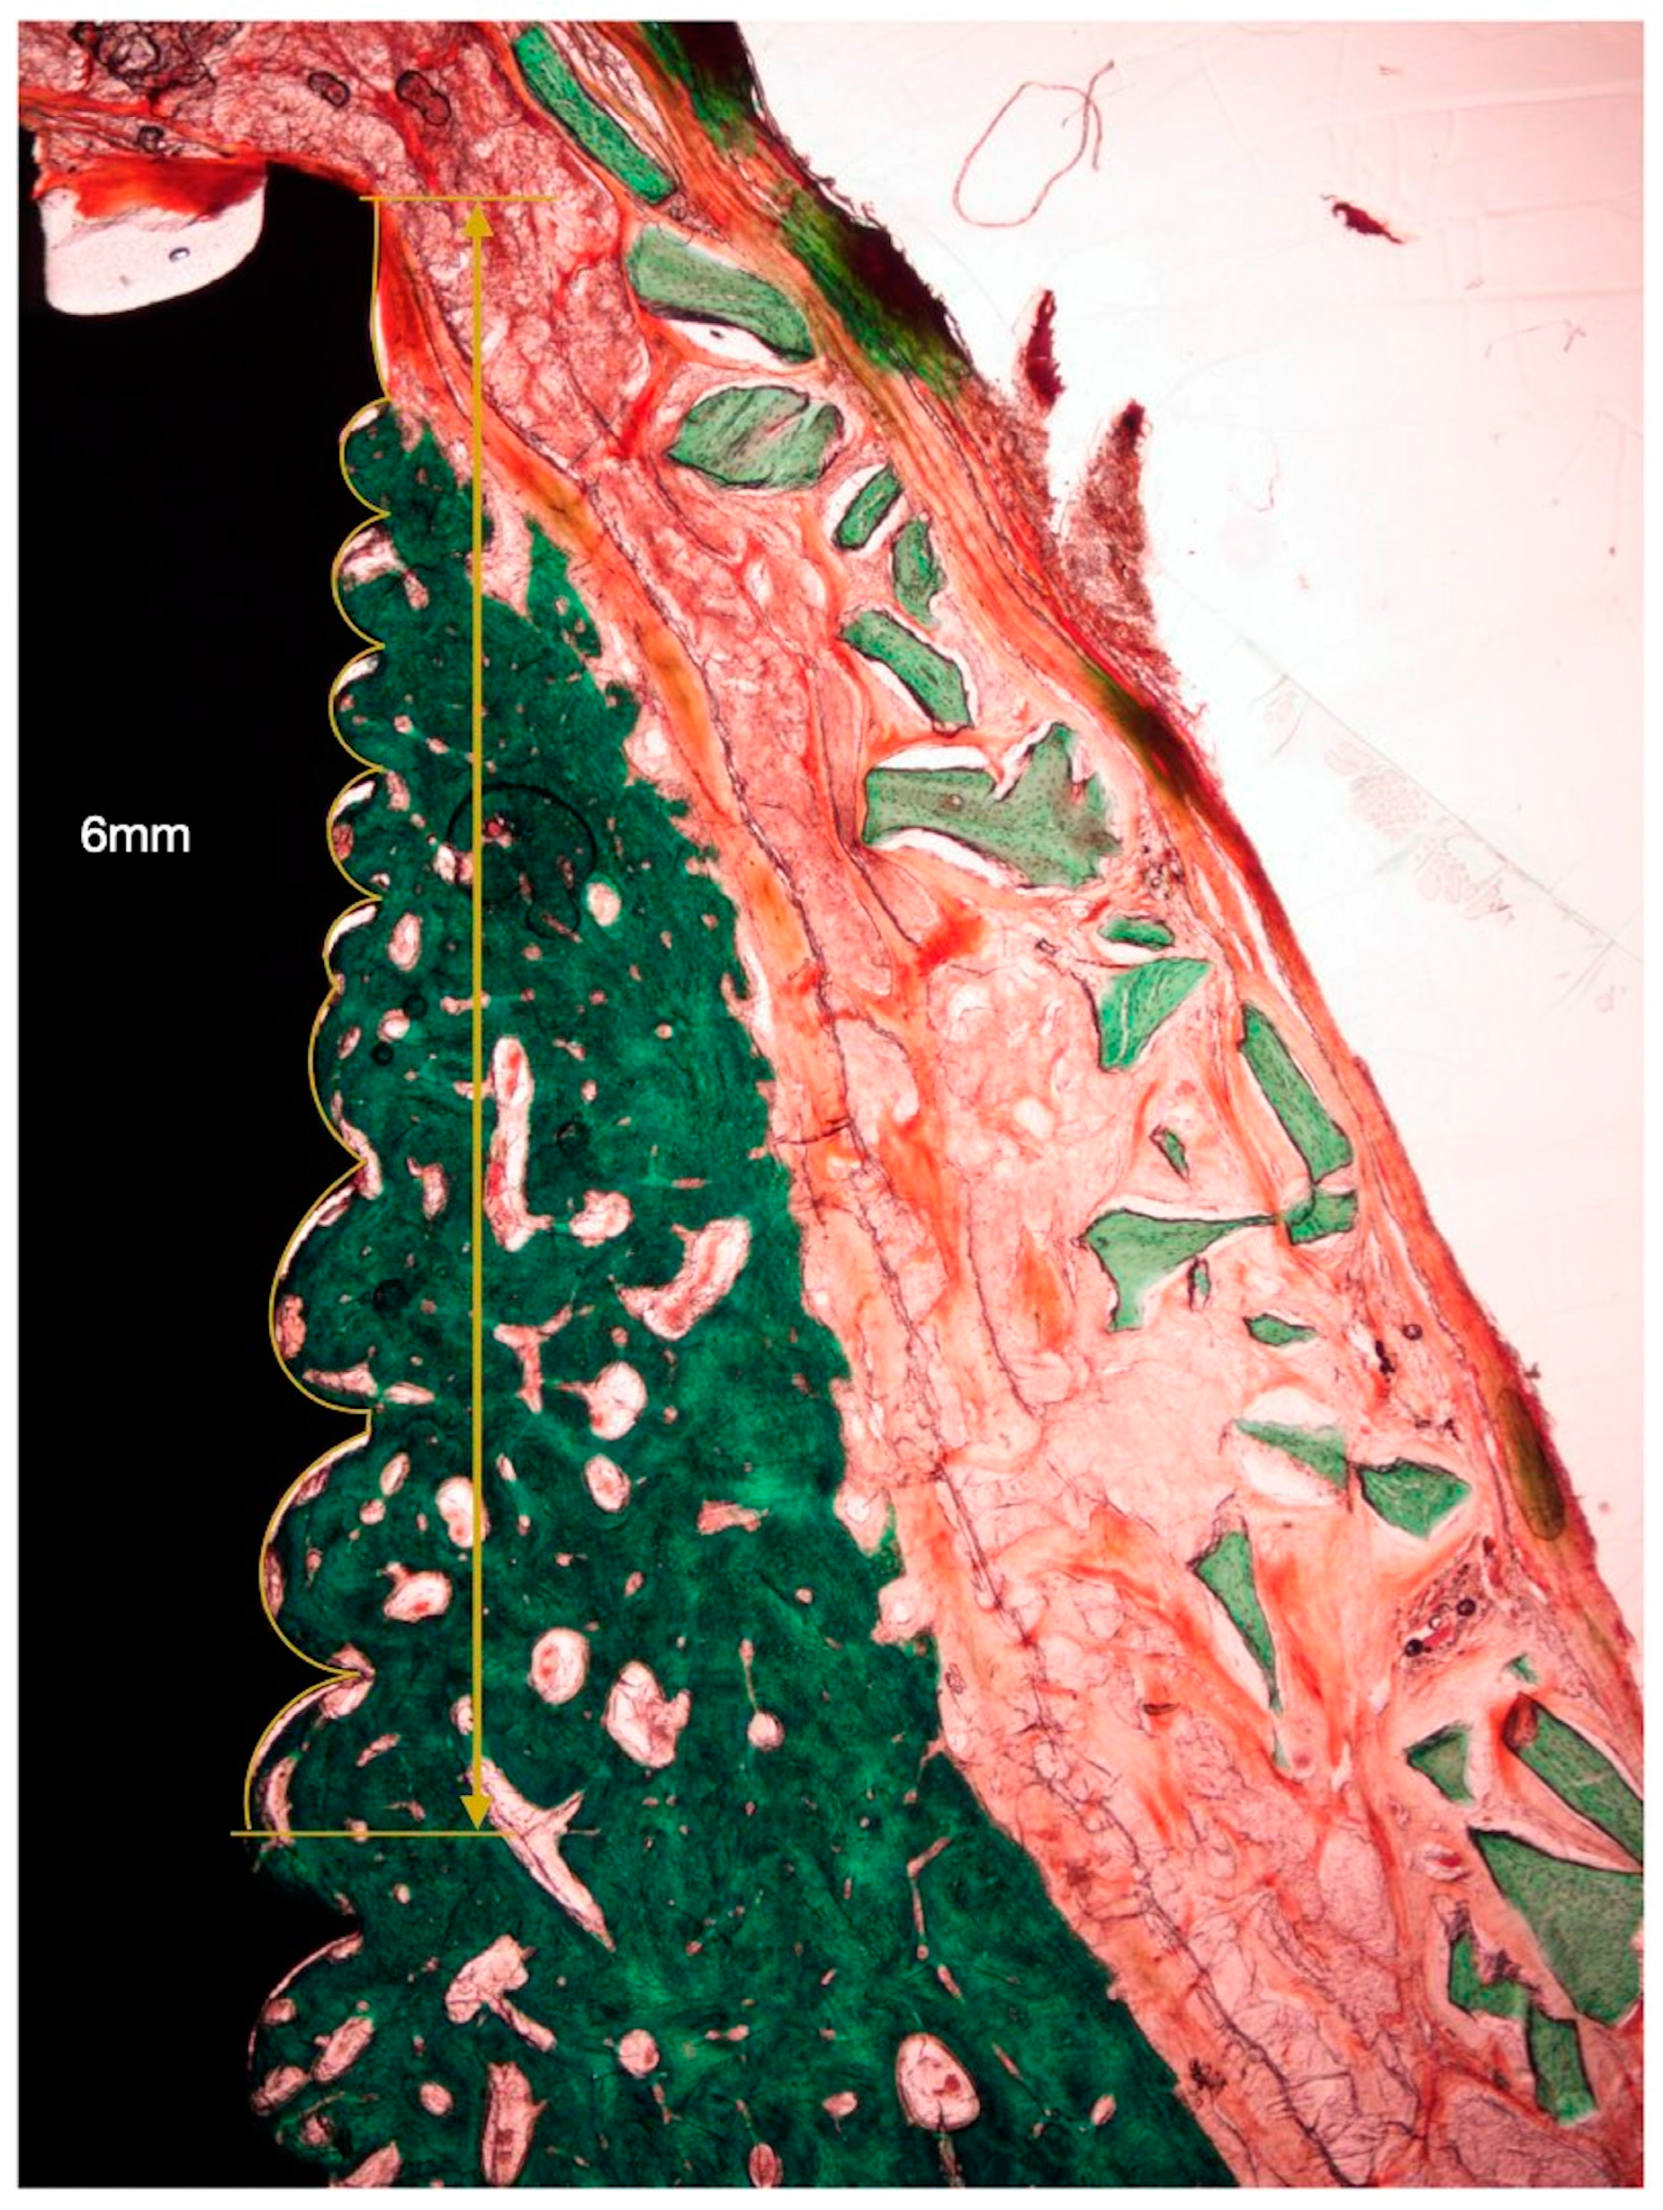

2.3. Histological Analysis

- NBT: Newly formed bone thickness at 1, 2, and 3 mm apical to the implant shoulder, described as the distance from the implant surface and the most buccal bone tissue.

- AGT: Augmented tissue thickness at 1, 2, and 3 mm apical to the implant shoulder (barrier space maintenance capacity), described as the distance from the implant surface to the inner part of the identified barrier membrane.

3.1. Histological Observations